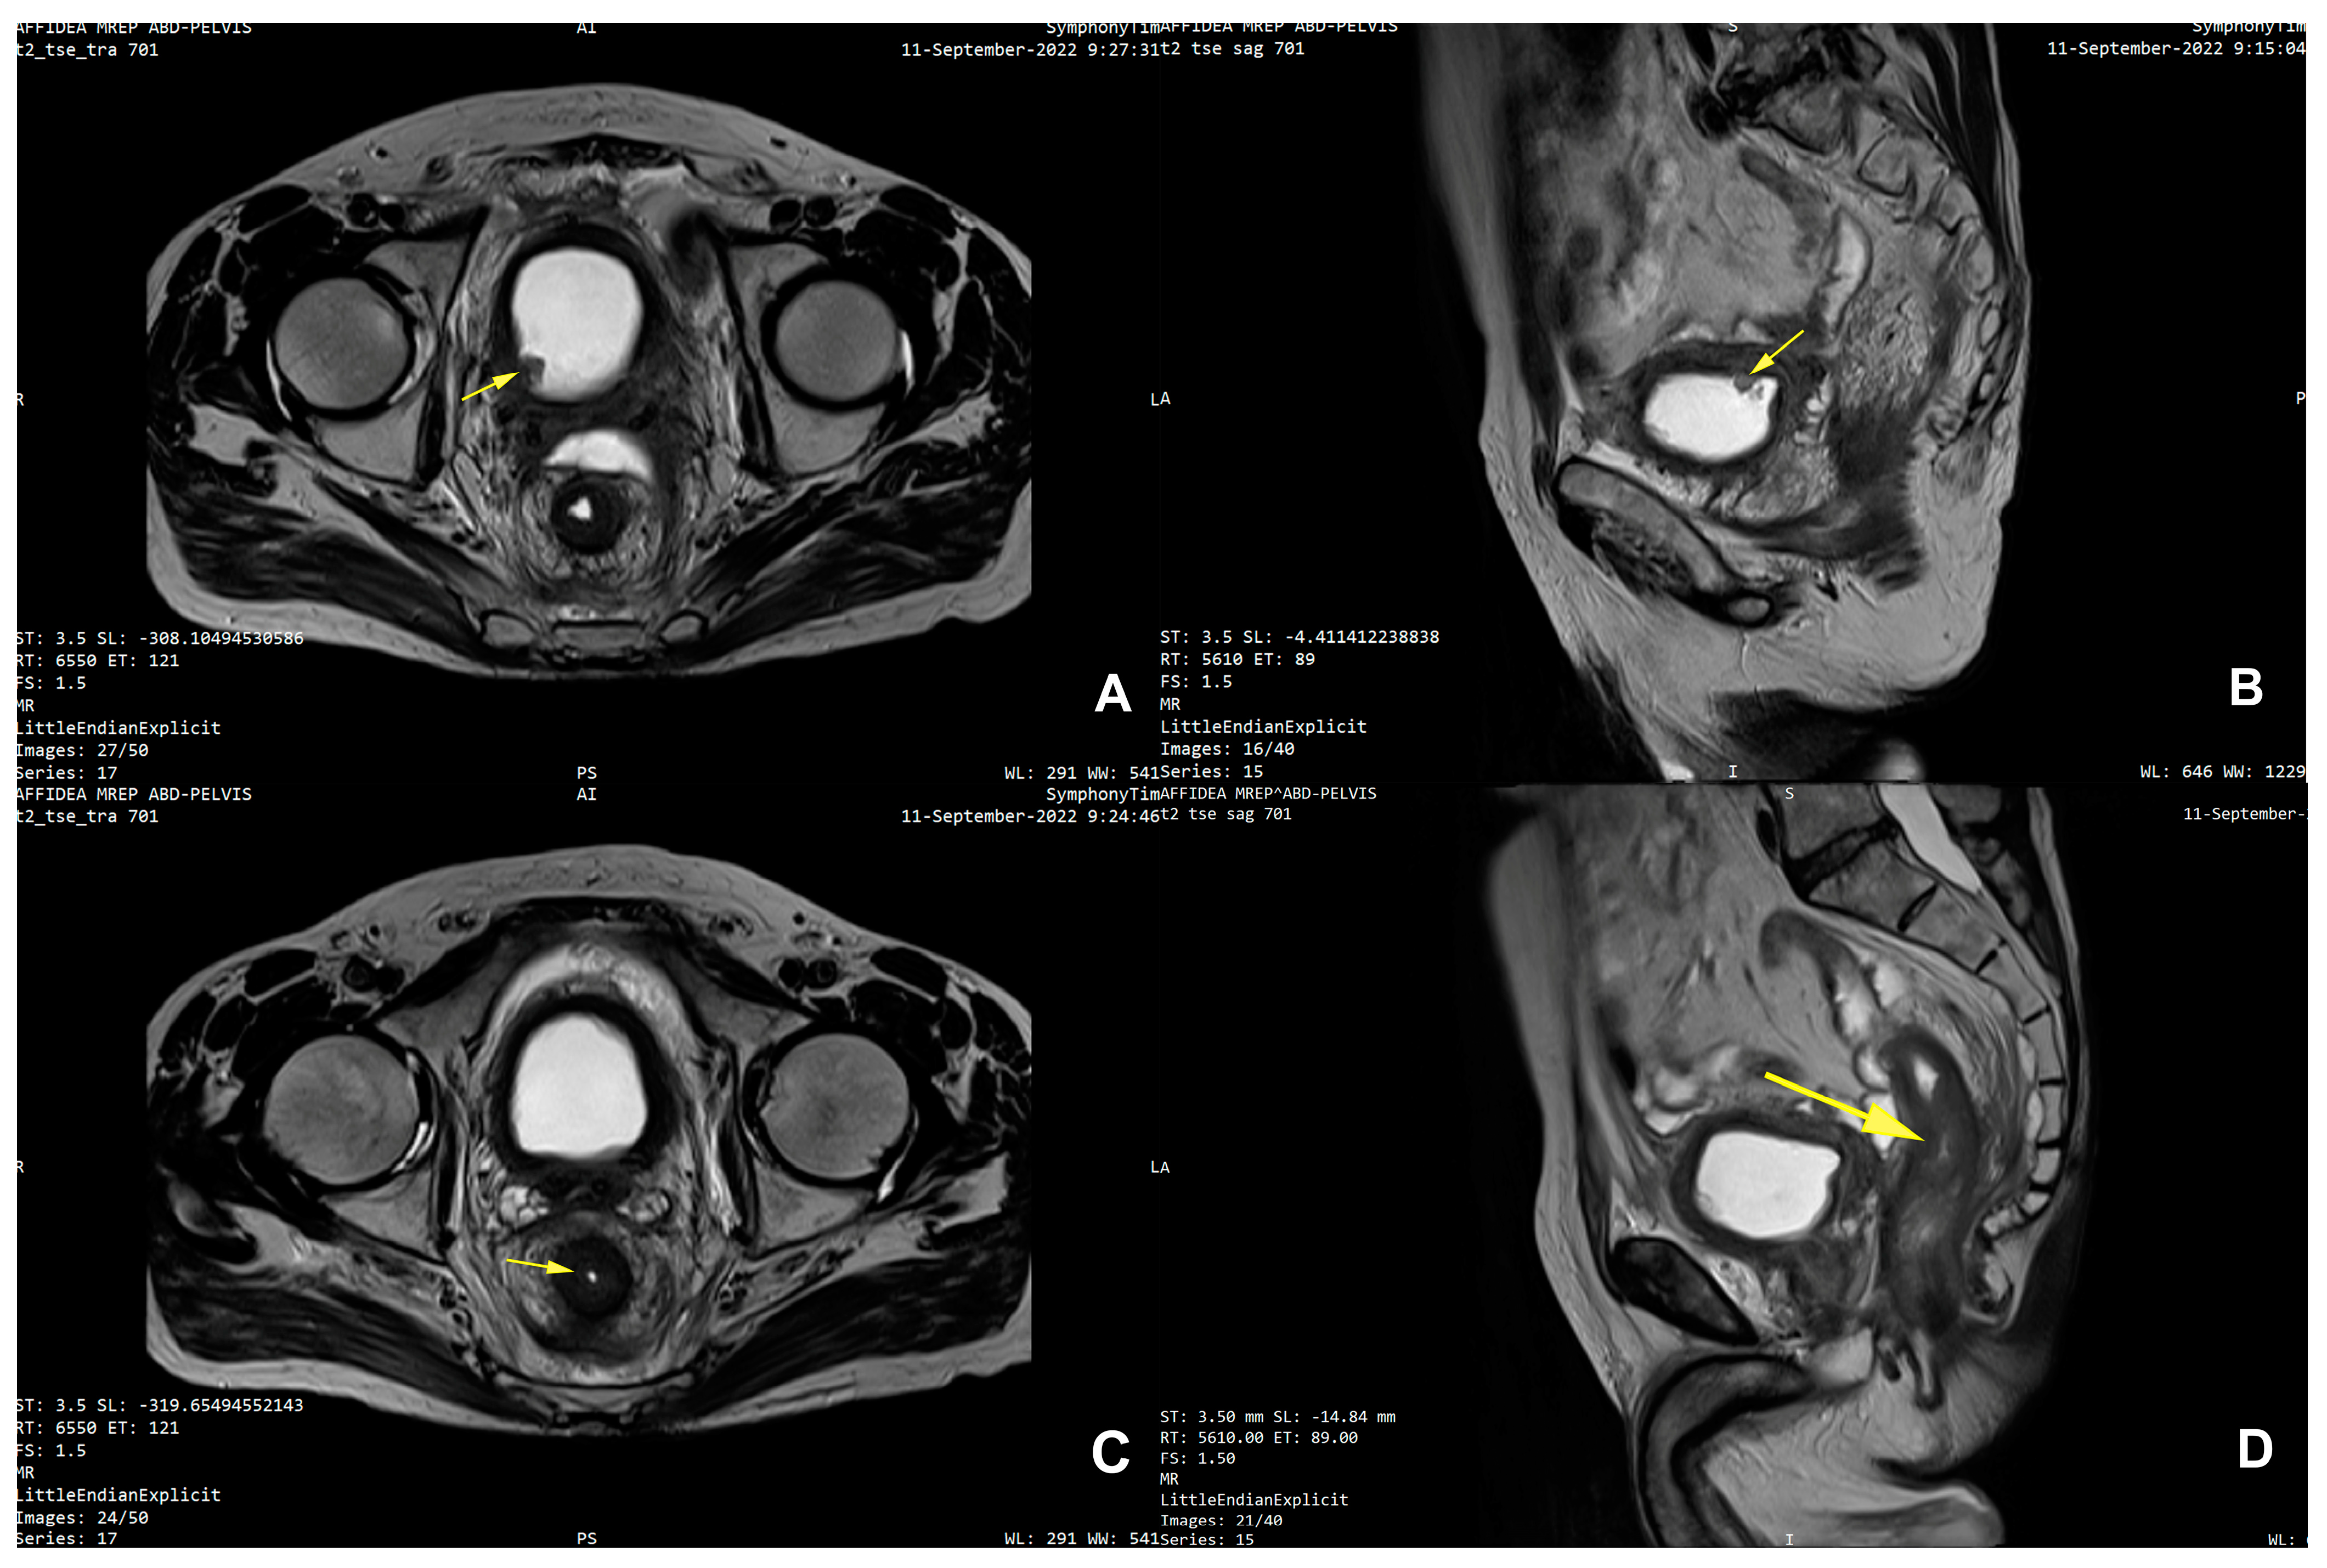

| 25 | Present Case (2025) | 64/M | UCC G3/conventional and signet ring cell | GATA3, CK 20/CK5/6, P63, CDX | colonoscopy, rectal EUS TCB | rectal tenesmus, transit disorders (constipation/small volume diarrhea), moderate dysuria | DISTAL MEDIUM R |

| 25. | Present Case (2025) | 64/M | 0 | NO | Colostomy, NEOADJ CHT GC, RT | 15 M/D | T2N0M0 |